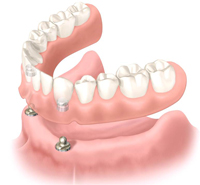

ボールアバットメントはオーバーデンチャーの中の1つの方法です。

インプラントの先のヘッドの部分が丸いボール形状になっており、入れ歯側に特殊な金具を付け、インプラントと入れ歯の部分をはめ込み連結させて固定します。

このボールアバットメントによるインプラント入れ歯は、ご自身でも簡単に取り外しができます。

このボールアバットメントオーバーデンチャーは、最低2本のインプラントで行うインプラント入れ歯です。使用するインプラント本数も少なく済むため、経済的にも優れた手法となります。